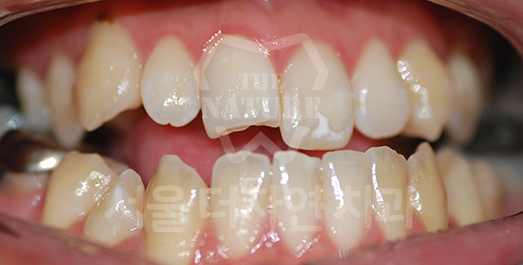

덧니 교정 Solution

덧니는 치아가 올라올 공간이 부족하여

제자리에 올라오지 못하는 상태를 말합니다.

덧니를 오랫동안 방치할 경우 칫솔질이 제대로 되지 않아

치아 사이에 음식물이 잘 끼고, 충치가 생길 위험이 큽니다.

또한 치주 질환의 원인이 되므로

교정치료를 통해 개선하는 것이 바람직합니다.

BEFORE: 2020.06.11

-